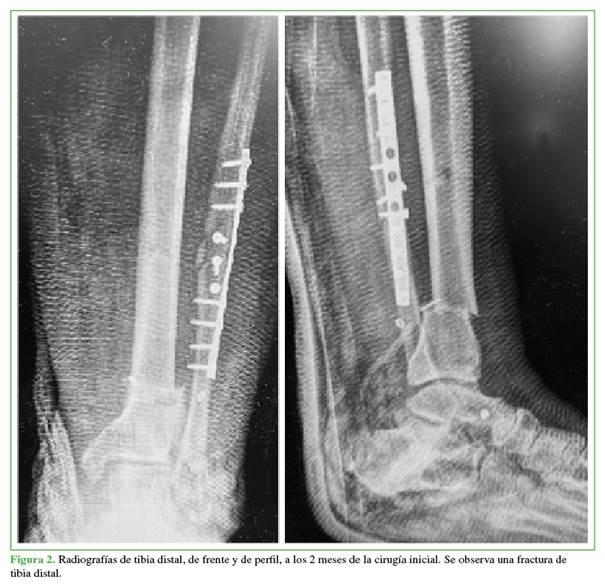

En enero de 2023, concurrió a nuestra institución donde recibió tratamiento para la fractura de tibia con clavo endomedular de ingreso maleolar (Figura 4). Se decidió utilizar un clavo endomedular de ingreso maleolar a causa de la mala calidad de las partes blandas en la zona anterointerna de la pierna y el índice de masa corporal elevado.9 La evolución posquirúrgica fue favorable, se constató la consolidación de la fractura de tibia a los cuatro meses del procedimiento quirúrgico.